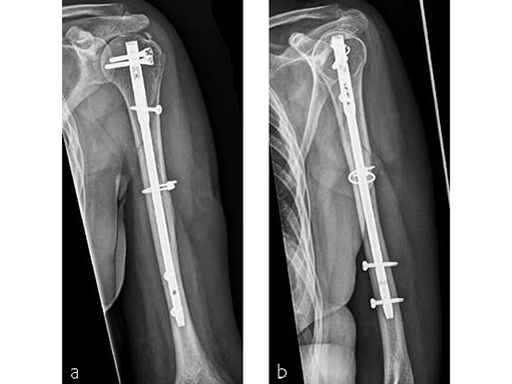

Case 1: AO 12C1 fracture following fall (Case provided by Stefaan Nijs, Leuven, Belgium)

A 54-year-old woman, and otherwise healthy patient, fell during her holidays and sustained an AO 12C1 fracture (Fig 1). There was no major soft tissue trauma. Other lesions: avulsion at the 5th metatarsal base, and concussion.

Surgery took place on day 9 after the accident. The patient left the hospital the day after surgery.